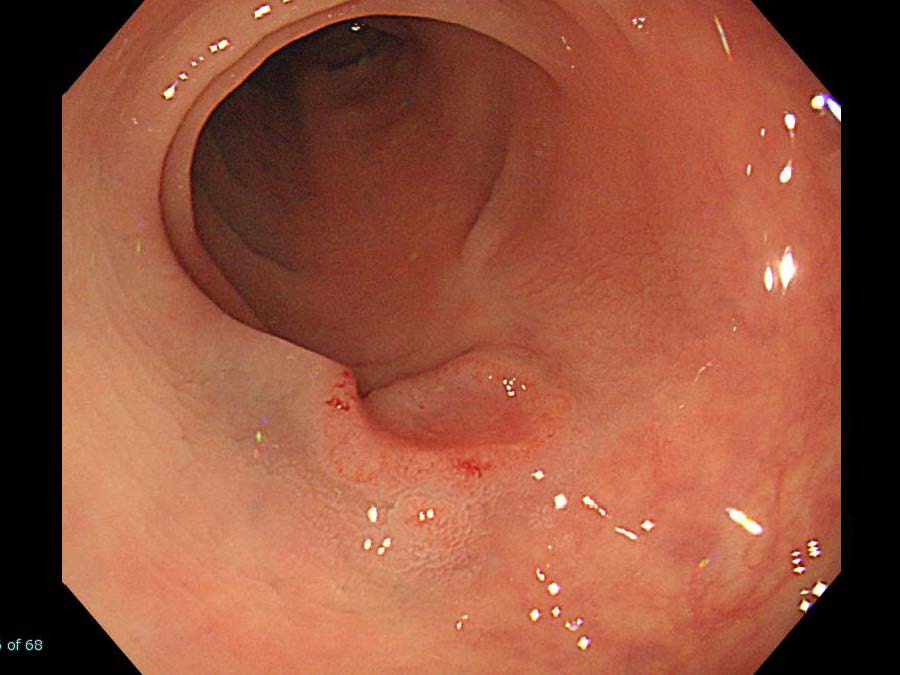

内視鏡検査・治療

消化管Mapping

消化管Mapping~大腸~

消化管Mapping~大腸~ 2021.10.27